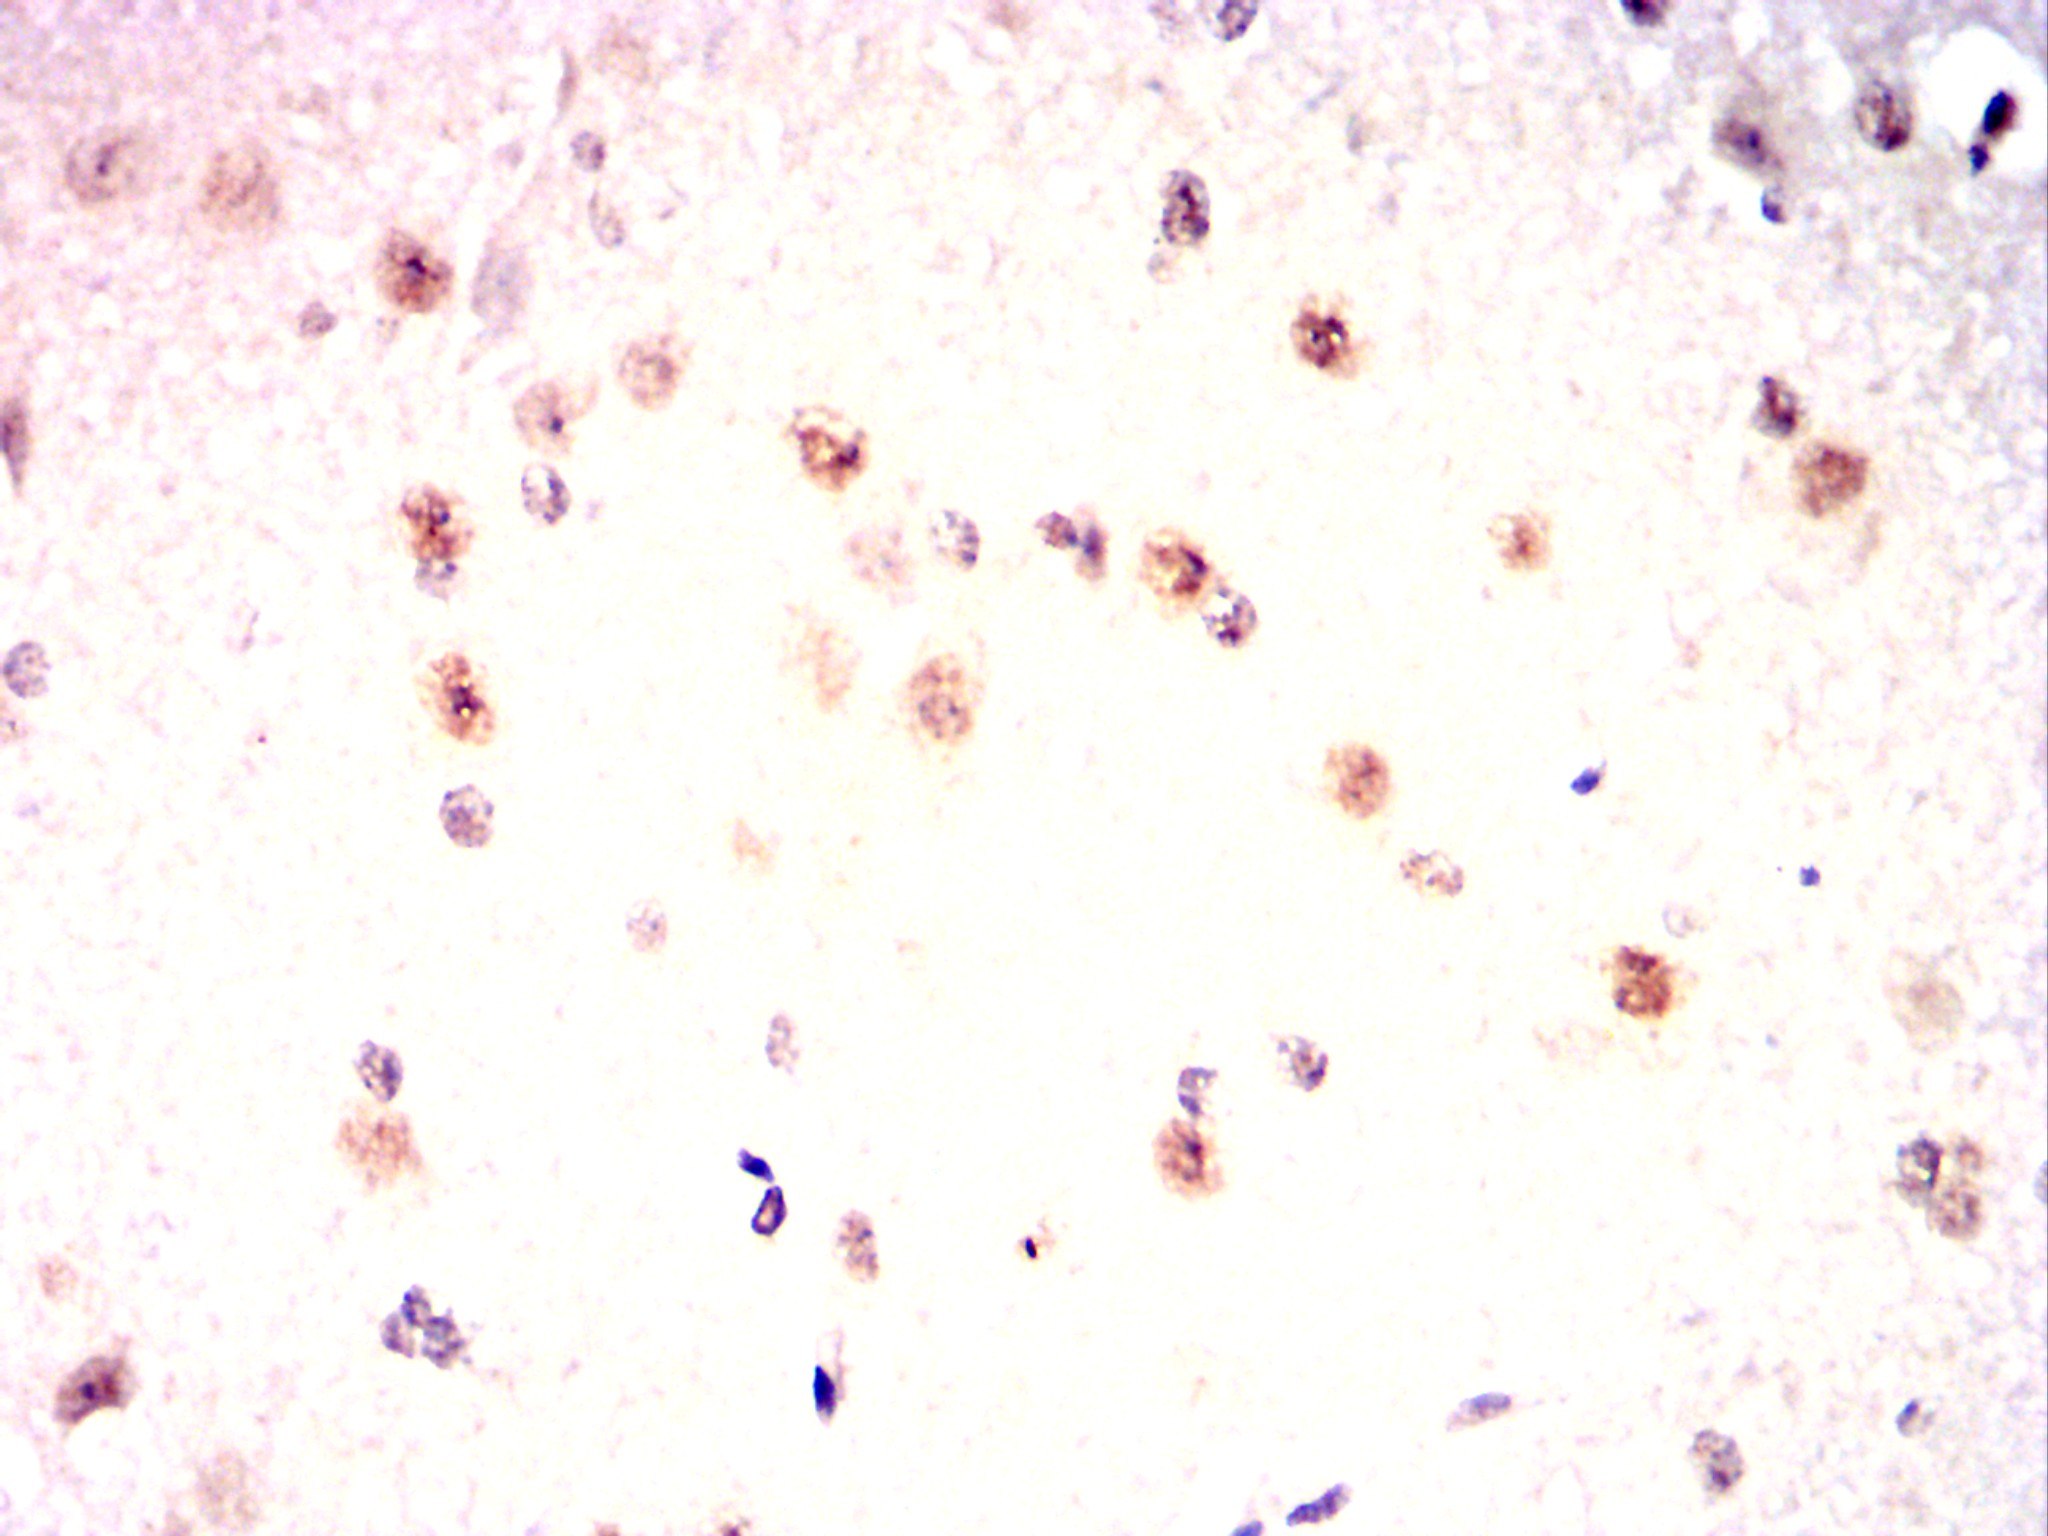

Immunohistochemical analysis of paraffin-embedded Mouse cerebellum using P2RX7 mouse mAb with DAB staining.